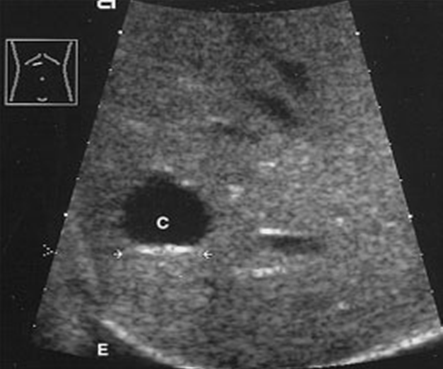

What is Simple hepatic cysts?

A hepatic cyst is usually a solitary, non-parasitic cyst of the liver. solitary or multiple. More common in females.

What is the sonographic appearance of hepatic cysts?

Solitary or multiple

Thin well-defined

walls

Anechoic

Posterior enhancement

Rarely fine,

linear internal septa, Calcification

What are the presenting symptoms of hepatic cysts?

Asymptomatic